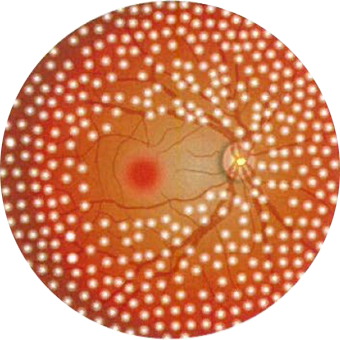

02.網膜レーザー光凝固

眼底出血した状態が長引くと、新生血管という異常な血管がでてくることがあります。新生血管とは通常の血管と比べると出血しやすく非常にもろい血管のことです。

この新生血管により様々な合併症を起こさなくするために、レーザー光凝固をします。

網膜の虚血部分へレーザー光を照射し、熱で凝固してしまう手術です。

これにより虚血部分の酸素の必要量が減り、そこに新生血管が伸びてくるのを防ぐことが出来ます。

この手術は受ける時期が早いほど効果が高く、早期で80%、時期が遅いと50~60%の有効率です。

1回の手術で数十から数百ヵ所凝固し、何回かに分けて照射することもあります。1個の凝固は0、2~0、5mmの円形のスポットで、カメラのフラッシュをたくような状況です。

尚、光凝固はあくまでも新生血管の発生を阻止し、進行を止めるのを目的としている手術です。既に視力が低下している場合はその時点の視力を維持する為に行われるもので、視力回復の手段ではありません。

黄斑部以外、ほぼ網膜の全体にレーザー光を当てる治療です。この治療により、新生血管が生じてくることを予防します。